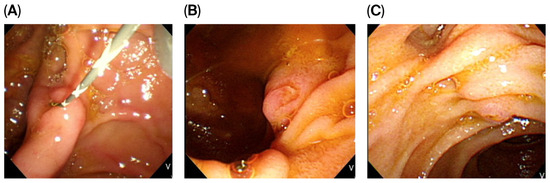

Impact of Papillary Morphology and Diverticular Type on Needle-Knife Papillotomy in Patients with Periampullary Diverticulum with Difficult Biliary Cannulation

by Kuan-Ting Liu, Sheng-Fu Wang, Chi-Huan Wu, Mu-Hsien Lee, Yung-Kuan Tsou, Cheng-Hui Lin, Kai-Feng Sung and Nai-Jen Liu

J. Clin. Med. 2025, 14(22), 8208; https://doi.org/10.3390/jcm14228208 - 19 Nov 2025

Background/Objectives: While previous studies have explored the relationship between periampullary diverticulum (PAD) and conventional endoscopic retrograde cholangiopancreatography (ERCP) success, data on advanced cannulation techniques like needle-knife papillotomy (NKP) remain limited. This study aimed to assess NKP outcomes in PAD patients with difficult biliary cannulation. Methods: A retrospective study was conducted on 122 PAD patients who underwent NKP in a single center. Patient characteristics, ERCP indications, common bile duct diameter, PAD type, diverticular size, major duodenal papilla (MDP) morphology, and post-ERCP adverse events were assessed. We also analyzed factors associated with the outcomes of NKP in patients with PAD. Results: Of the 122 patients, NKP was successful in 82 (67.2%) and failed in 40 (32.8%), with diverticular diameter being significantly larger in the failure group. By PAD type, the diverticular median diameters were 1.2 cm (type I), 0.9 cm (type II), and 0.5 cm (type III) (p < 0.001), with NKP success rates of 50%, 66.3%, and 75%, respectively (p = 0.391). By MDP morphology, the success rates were 73.7% (type I), 38.2% (type II), 92.9% (type III), and 82.4% (type IV) (p = 0.059). The overall adverse event rate was 16.4%, with pancreatitis (6.6%), bleeding (5.7%), and cholangitis (4.1%) showing no significant differences between the success and failure groups. Multivariate analysis identified MDP morphology (type II vs. I, OR: 0.256, p = 0.011) and active bleeding during NKP (OR: 0.117, p < 0.001) as independent predictors of failure. Conclusions: MDP morphology and intraprocedural bleeding are significant independent predictors of NKP failure in PAD patients with difficult biliary cannulation, whereas PAD type has no significant impact on NKP outcomes. Full article